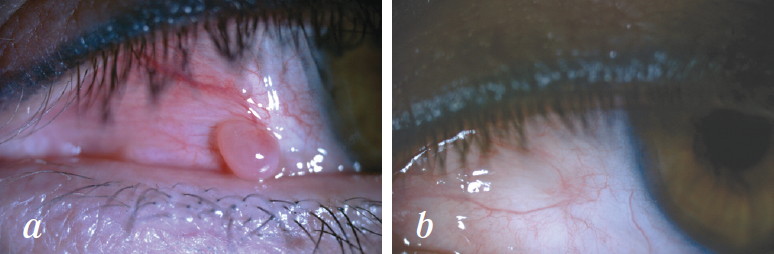

Рис. 1. Пациент Х., 70 лет. Диагноз: «Атерома (триходермальная киста) века»: a — до операции; b — спустя 1 месяц после криодеструкции опухоли

Fig. 1. Patient Kh., aged 70, diagnosed with eyelid atheroma (trychodermal cyst): before surgery (a) and 1 month after tumor cryodestruction (b)